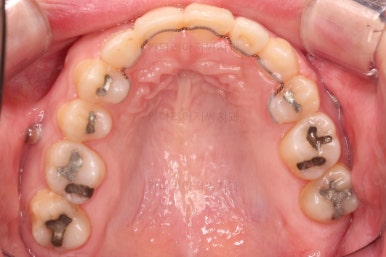

장치를 구성합니다.

이번 환자분은 윗니는 세라믹, 아랫니는 메탈 장치를 선택하셨는데요.

둘 다 물론 자가결찰 장치였고요.

동일한 제품의 장치이므로 혼용해서 쓰는게 가능합니다.

많이 보이는 부분은 세라믹, 잘 안보인다고 여겨지시는 부분은 메탈로 선택하면서 치료비 측면도 함께 고려한거죠.

장치 부착 직후의 모습인데요.

윗니는 가지런하게 한 뒤 발치공간을 서서히 닫아줍니다.

유치는 크기가 작았기 때문에 생각보다 빨리 공간이 닫히고 있고요.

반대쪽 작은 어금니 부분은 공간이 아직 많이 남은 편이죠.

적절하게 틈도 다 모아주고요.